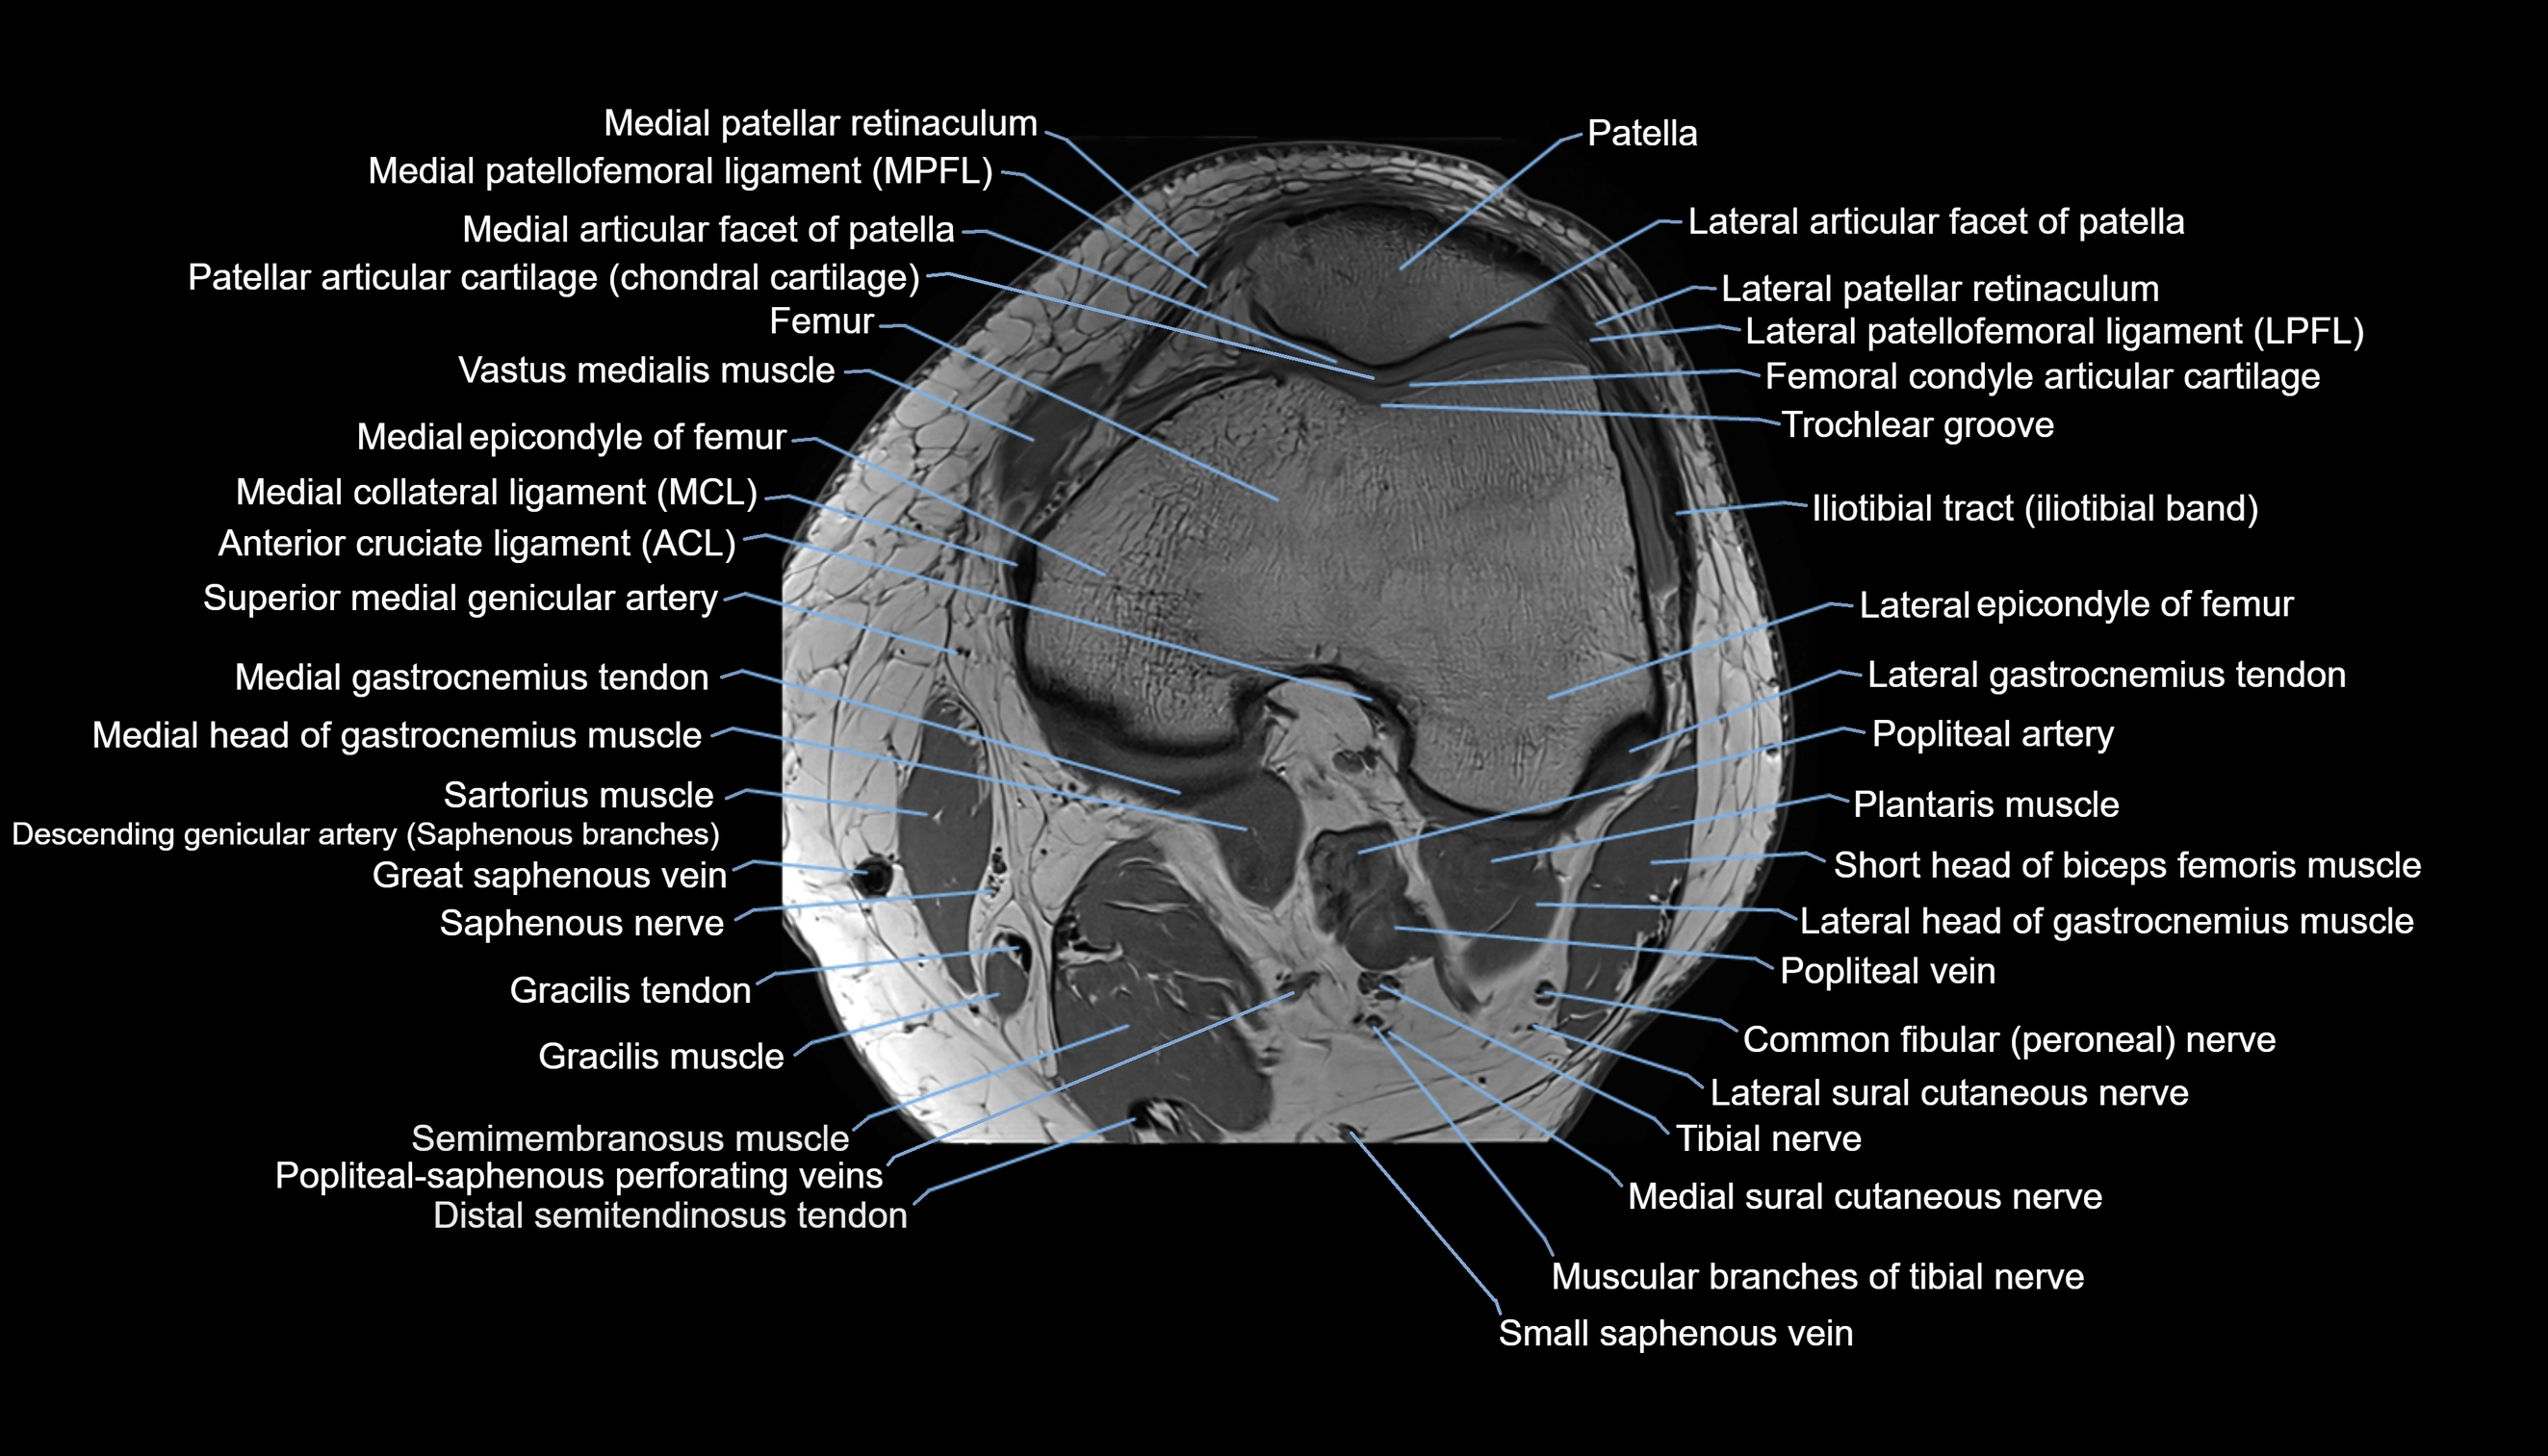

- Anterior cruciate ligament

- Biceps femoris muscle (Short head)

- Common fibular nerve

- Descending genicular artery (Articular branches)

- Distal semitendinosus tendon

- Femoral condyle articular cartilage

- Gracilis tendon (Distal)

- Lateral articular facet of patella

- Lateral epicondyle of femur

- Lateral gastrocnemius tendon

- Lateral head of gastrocnemius muscle

- Lateral patellar retinaculum

- Lateral patellofemoral ligament

- Lateral sural cutaneous nerve

- Medial articular facet of patella

- Medial collateral ligament

- Medial epicondyle of femur

- Medial gastrocnemius tendon

- Medial head of gastrocnemius muscle

- Medial patellar retinaculum

- Medial patellofemoral ligament

- Medial sural cutaneous nerve

- Muscular branches of tibial nerve

- Patella

- Popliteal artery

- Popliteal vein

- Popliteal–Saphenous perforating veins

- Sartorius muscle

- Small saphenous vein

- Tibial nerve

- Trochlear groove

- Vastus medialis muscle

- great saphenous vein